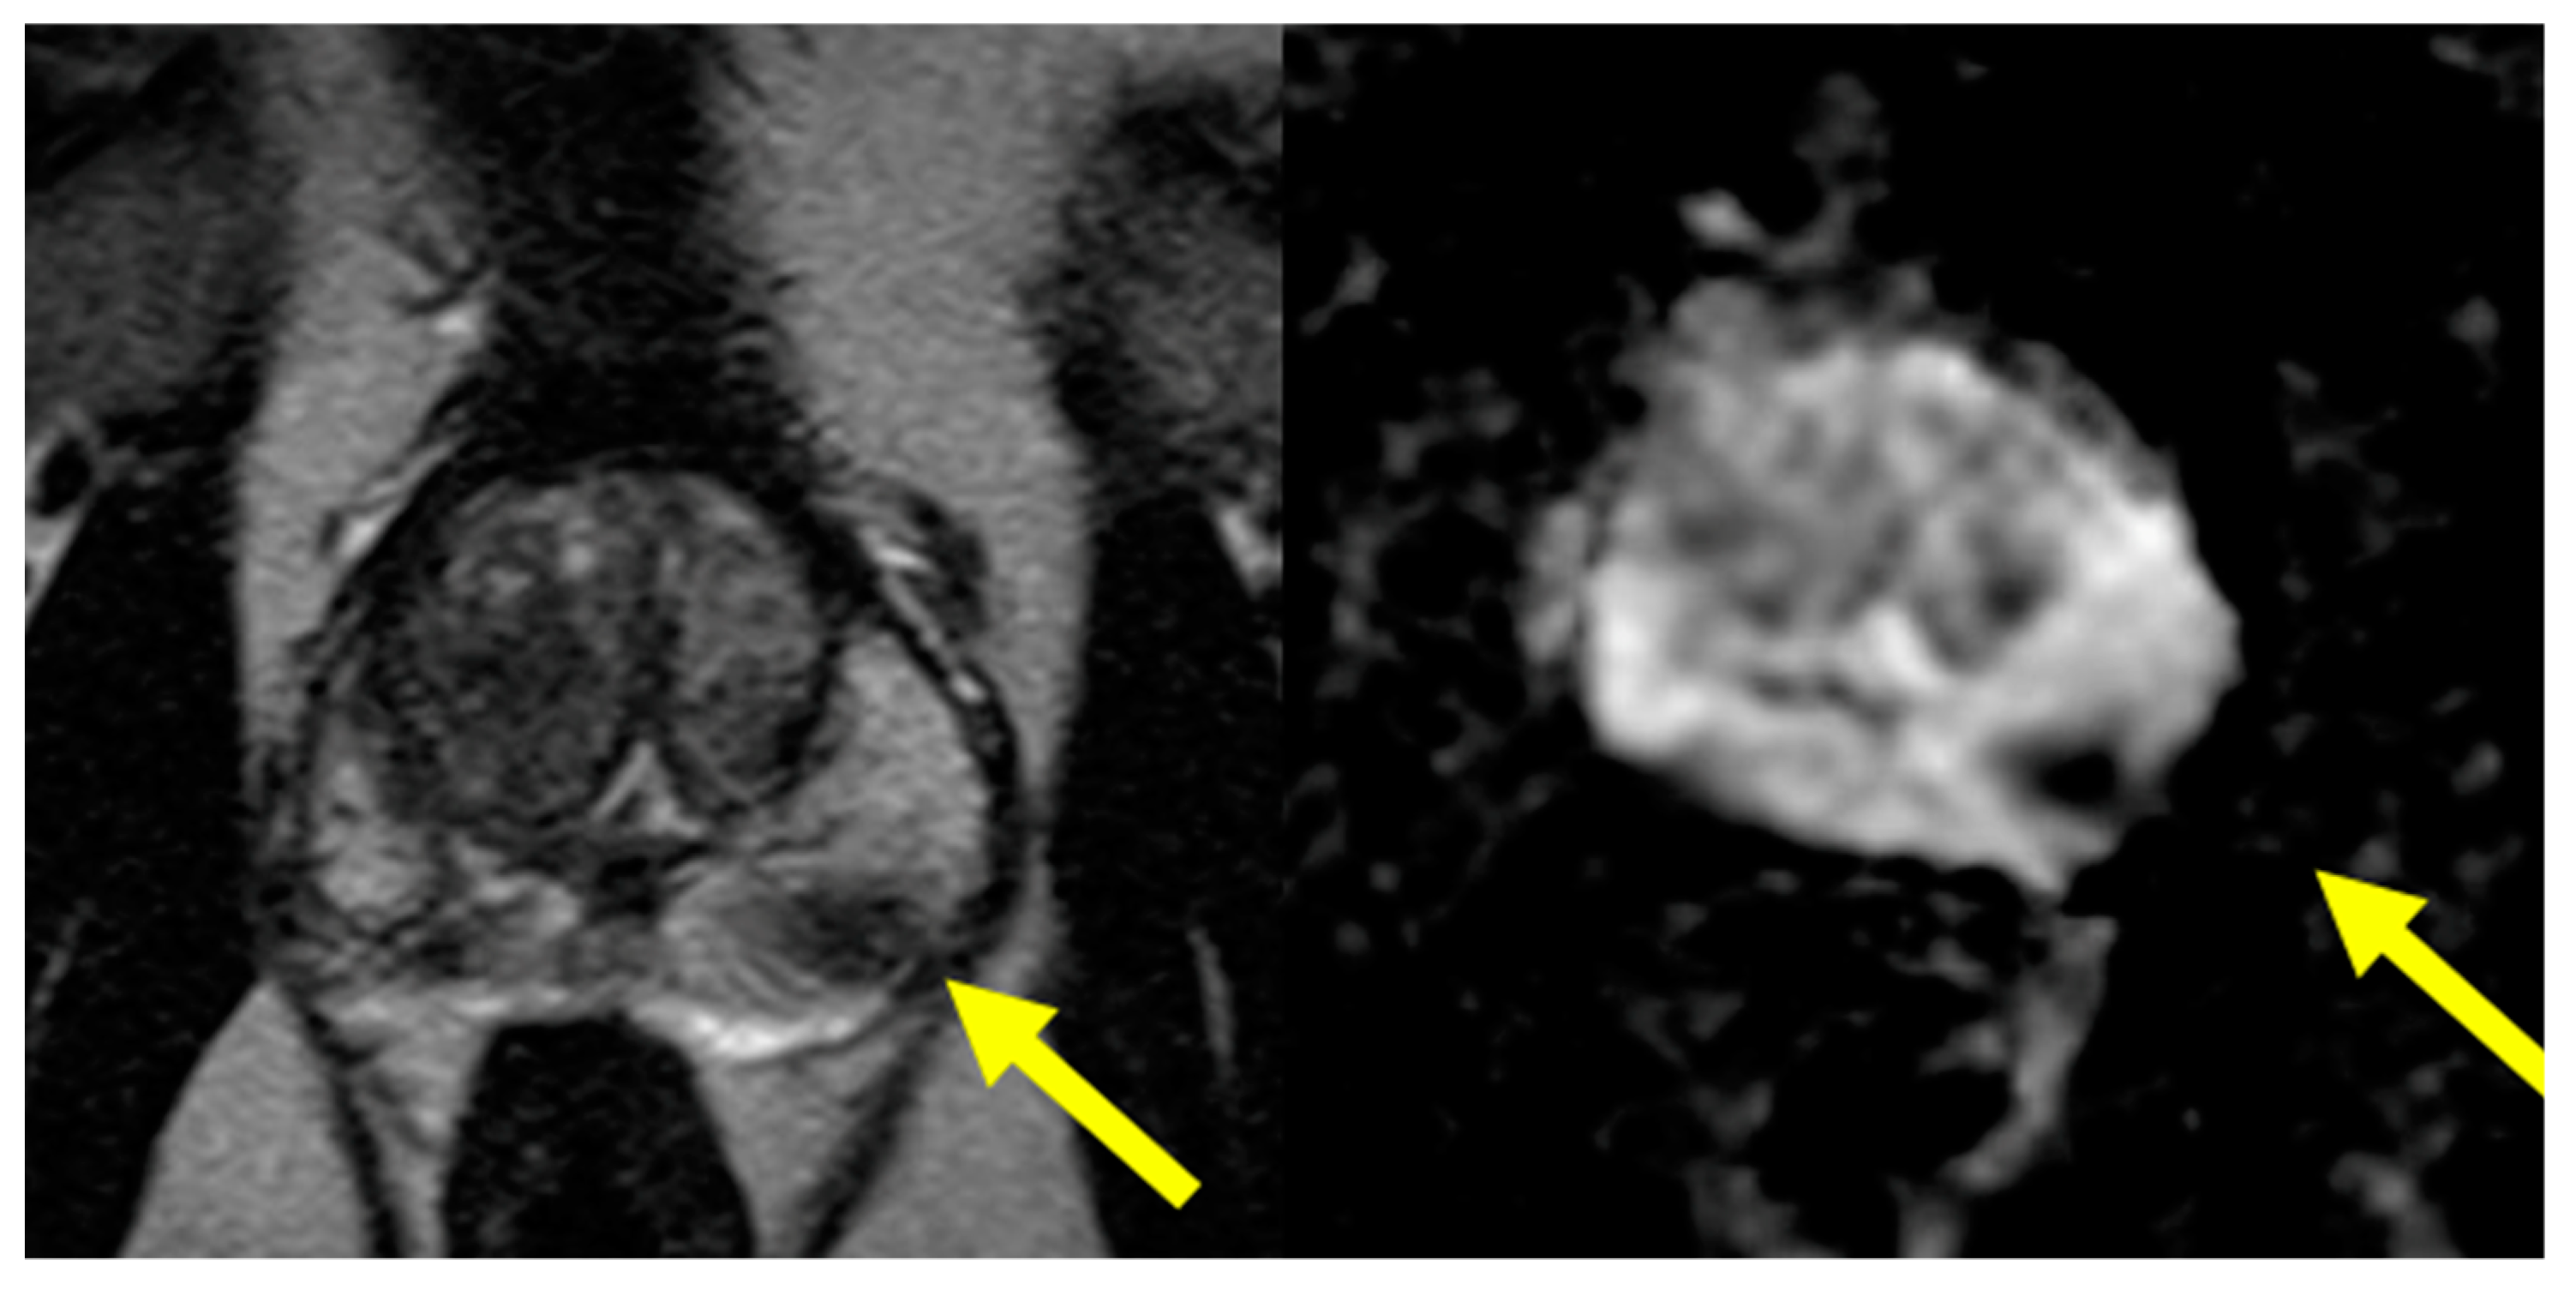

The following is a case presentation and description of an mpMRI-guided biopsy via the TP approach performed at our institution. A 62-year-old male presented with a rise in prostate specific antigen (PSA) from baseline ~2 to ~7. The patient underwent 3.0 T mpMRI, which demonstrated a PI-RADS 4 lesion in the left posterior mid-gland that can be seen on T2-weighted (Figure 1, left) and ADC images (Figure 1, right).

Figure 1.

Axial T2-weighted (left) and axial ADC images (right) with arrow identifying the ROI.